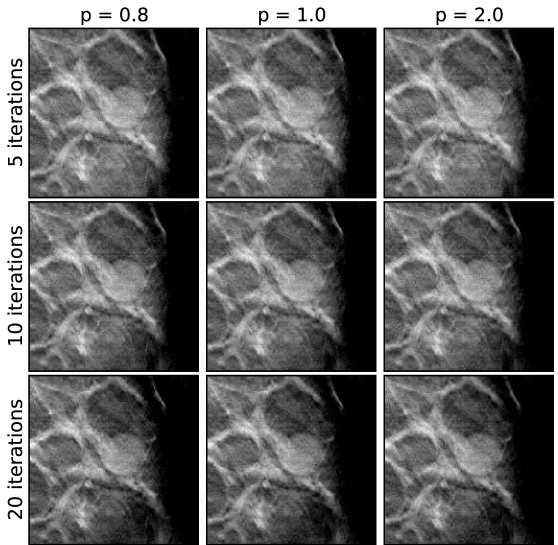

Each of the three cases, below, are reconstructed in the same way, meaning the same sets of algorithm parameters are used. The exceptions to this are that the image volume dimensions and the projection data cropping are slightly different for each case. For the EM results images are shown at 5,10, and 20 iterations, as iteration number is really the main control for regularization. For ASD-POCS, the objection function parameter is set to 0.8, 1.0, and 2.0; lower values of tend to sharpen edges. The relaxation factor takes on values of 1.0, 0.5, and 0.1; smaller , in general, allows for ASD-POCS to achieve lower values of the TpV objective. Images for ASD-POCS are also shown for 5, 10, and 20 iterations. As will be seen, there is surprisingly little change in the reconstructed images for these iteration numbers. In each of the image sets, a 2D ROI is displayed that shows either microcalcifications or a mass, depending on the case.

V.5 Case 2: uniform mass

For the next case, there is a uniform mass, as can be seen in the EM image-reconstructions in Fig. 9. As was done in the previous case, we present a spread of images in Figs. 10, 11, and 12 from the ASD-POCS algorithm for the same sets of algorithm parameters, covering a range of - and -values. The iteration number dependence appears to be weak for ASD-POCS. The conspicuity of the mass for this case does not vary with algorithm parameters nearly as much as the microcalcification conspicuity of the previous case. There are many reasons for this. First, the X-ray attenuation coefficient of the mass is less than that of calcium, so the contrast that can be potentially regained is not as great. Second, the lower reconstructions tend to yield sharper edges, but this does not have as large an effect on the mass which is substantially bigger than microcalcifications. Finally, as pointed out earlier, mass conspicuity tends to depend on background structure noise. As this type of background is physically there, low image-reconstruction sharpens the edges of the background features just as much as the mass’s edges. Thus, the conspicuity of the mass may not improve dramatically as is lowered. In any case, there are subtle differences between the images, and these differences may have an impact on human or machine observers.

Comparing the visual quality of the images of the present case with the previous one, it is interesting that similar -values do not yield similar apparent image quality. For example, for the present case appears to be quite noisy, even taking into account differing gray level windows, relative to for the previous case. For the 3 sets of -values, appears to yield, visually, the best images for this mass case, while seems to best for the previous, microcalcification case. These, differences are likely due to varying quality of the acquired projection data. A quantitative discussion of algorithm performance across different DBT cases will be further elaborated on in Sec. V.7.